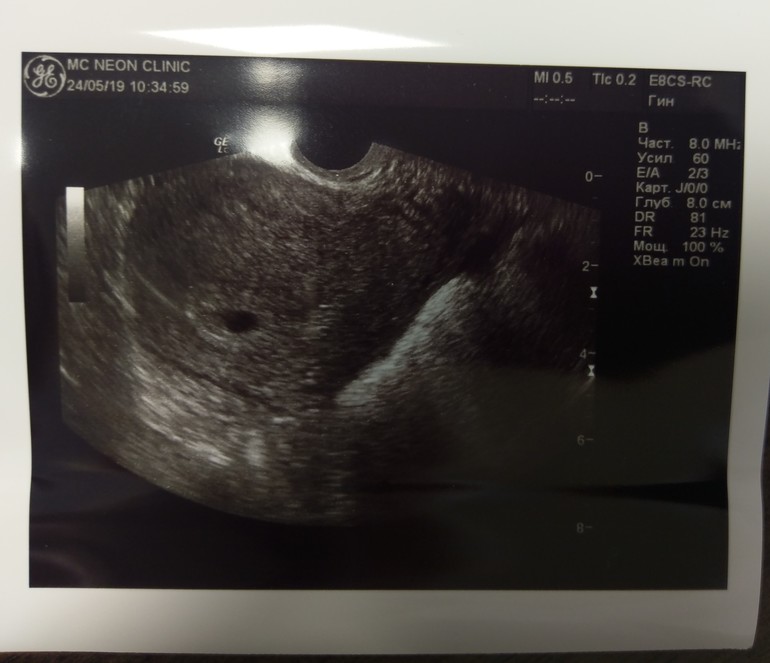

Я ходила в 4+0 сказали хороший эндометрий и шикарное ЖТ. Шейка беременная (синюшная). Естно никакого ПЯ не было. Потом в 5+0 сказали приходить, чтобы исключить ВБ. Нашли ПЯ. Сказали приходить через неделю искать малышастика уже. А я думаю рано. Фото с узи в пять недель ровно.